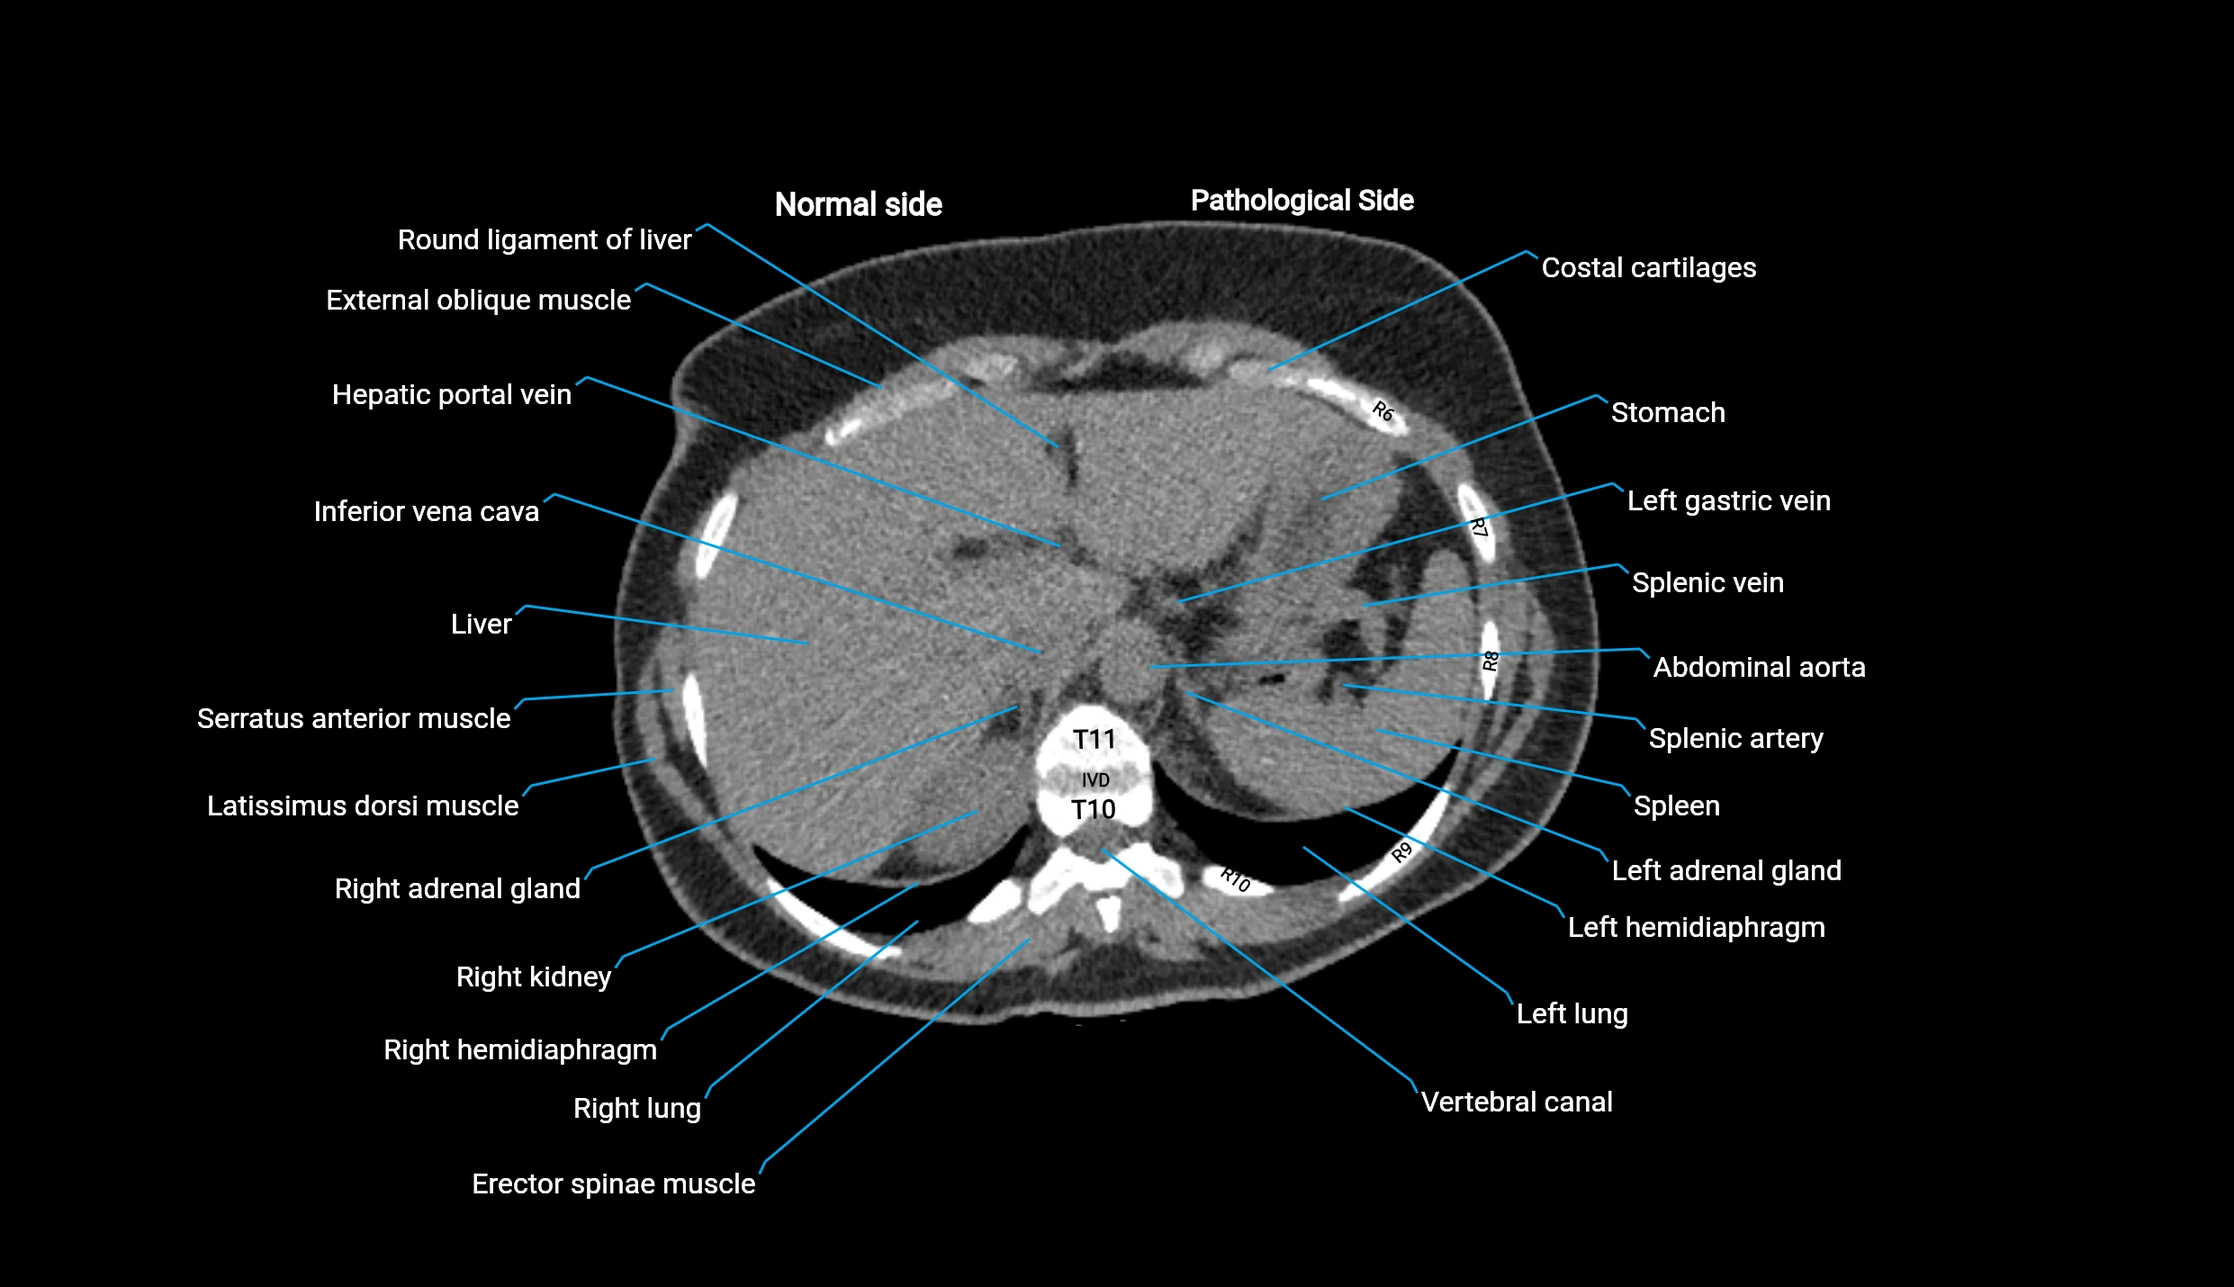

Post-Contrast CT (Contrast-Enhanced CT):

• Portal venous phase:

• Anterior right portal branch enhances intensely and homogeneously

• Clearly separates from posterior branch

• Branching pattern to segments V and VIII sharply defined

• Arterial phase:

• Slight enhancement but less conspicuous than in portal phase

• Coronal and sagittal reconstructions:

• Optimal visualization of segmental bifurcation

• Used for preoperative liver mapping

• CT liver segmentation:

• RAPV acts as the principal boundary landmark for dividing anterior vs. posterior right hepatic segments